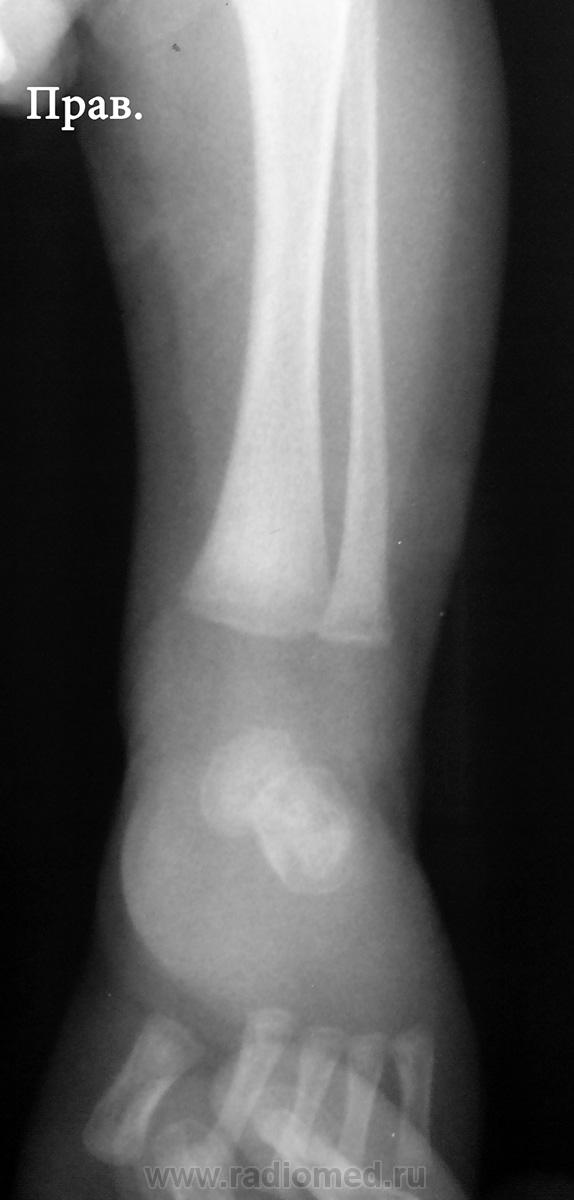

Ребенку 2-3 недели, лежит у нас по поводу остеомиелита. Дней 7 назад - появились отек, болезненность левого голеностопа, про анализы, к сожалению, ничего сказать не могу. Получил курс антибиотиков, отек спал.

В проксимальных метафизах большеберцовых - такие же полоски.

Давно не встречалась с врожденным костным сифилисом, лет 10, позабылось все (раньше, в другой больнице, видела его достаточно часто), но что могу сказать - полосы просветления в метафизах (а также полосатость ядер окостенения пяточной и таранной костей) встречаются не только при сифилисе, часто видела их у здоровых недоношенных;  при сифилисе, кроме этих полос, должно быть расширение и зазубренность зон предварительного обызвествления, симметрично в костях голеней и предплечий, клинически, обычно, не проявляется, только при третьей стадии остеохондрита, когда появляются псевдопараличи Парро - появляется припухлость, отек, ограничение движений, и это также с обеих сторон. Здесь мне видится нечеткость метафиза малоберцовой кости слева, скорее всего, обычный остеомиелит. Конечно, анализ на сифилис, все-равно, заказать надо.

К малоберцовке тоже придрался, тем более и клиника именно там была.